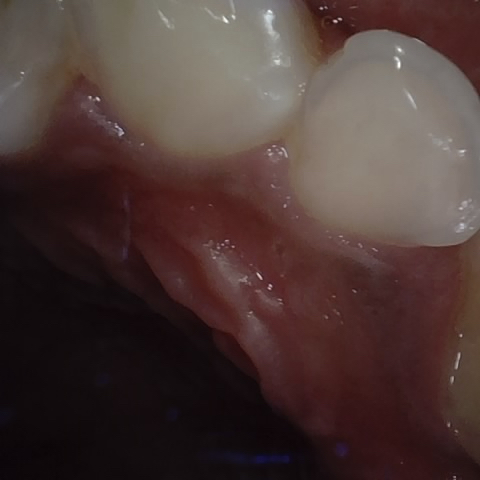

NHD39174

Annotated as "Good"